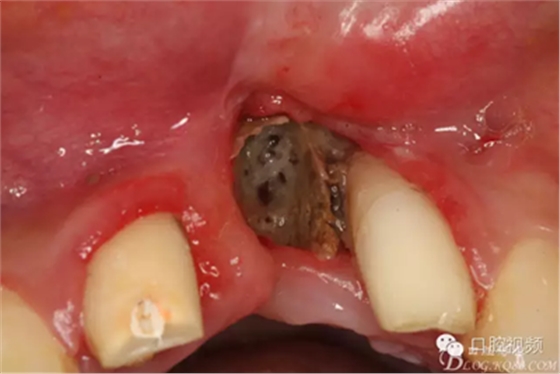

圖1.21唇側(cè)牙齦潰爛。牙槽骨暴露成灰褐色,22近中根面外露。

圖6.拆除前牙烤瓷橋后,21區(qū)域死骨清晰可見,22牙根暴露2/3,觸目驚心!